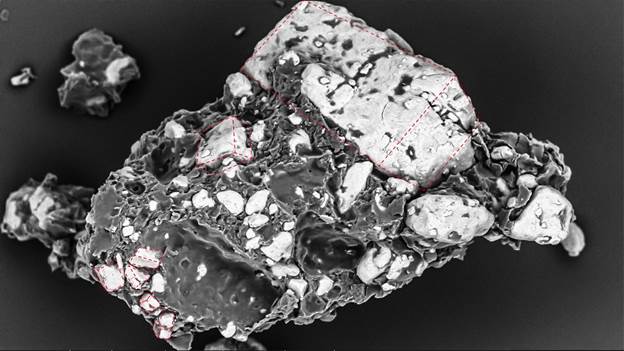

При разработке таблеток с пролонгированным высвобождением на основе гидроксипропилметилцеллюлозы (ГПМЦ) методом СЭМ было установлено, что измельченные частицы хлорида калия (сохраняющие фрагменты кубической формы) равномерно распределены и прочно связаны непрерывной гелевой матрицей ГПМЦ. Граница раздела фаз характеризуется хорошей адгезией, структура отличается плотностью и низкой пористостью (рис. 2b). Такая плотная упаковка замедляет проникновение жидкости и обеспечивает диффузионно-контролируемое высвобождение, что согласуется с моделью Хигучи – математическим уравнением, описывающим высвобождение лекарственного вещества из твердой матричной системы.

Рис. 2b — Таблетка хлорида калия с пролонгированным высвобождением: частицы АФИ (сохранившие части кубической огранки) интегрированы в плотную гелевую матрицу ГПМЦ. Изображение получено с помощью СЭМ LANSEM 30.